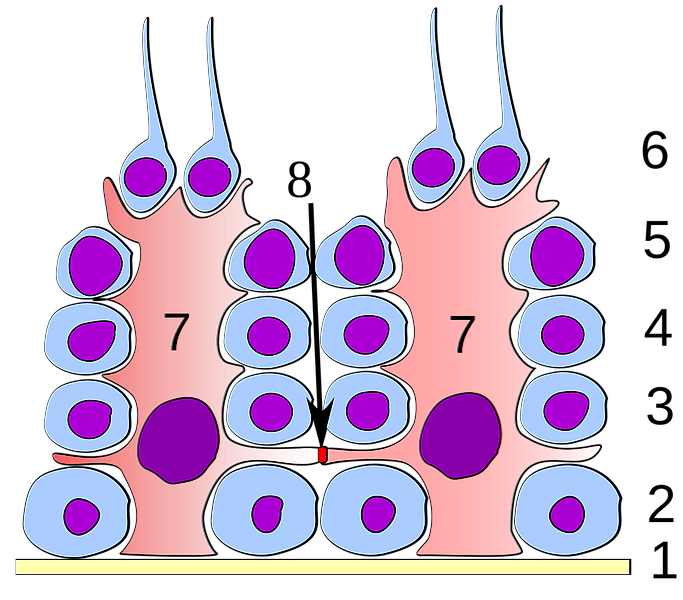

Sertoli cells

- Complex columnar shape

- Basal lamina to lumen

- Irregular outline

- Envelope developing germ cells

- Large pale nucleus with indentations & large nucleolus

- Occludens junctions with adjacent cells

- Establish blood-testis barrier

Spermatogenic cells

- Several stages of spermatogenesis

- Spermatogonia

- Primary spermatocytes

- Secondary spermatocytes

- Spermatids

- Spermatozoa

Spermatogonia

- Diploid

- Sits on basal lamina

- 3 types

- Pale type A

- Small, pale nucleus

- Produce pale type A or type B

- Dark type A

- Dark nucleus

- Reserve cell to produce pale type A

- Type B

- Undergo mitosis

- Form primary spermatocytes